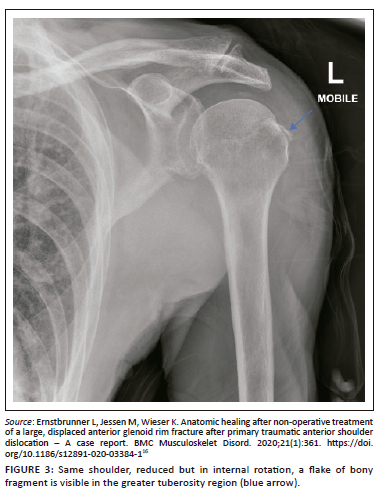

Control plain radiographs are mandatory. Three views must be obtained (anteroposterior, axillary view and lateral view) to confirm the reduction and rule out bony compression fractures of the humeral head (Hill-Sachs lesion), push-off fractures of the glenoid (bony Bankart lesion), bony erosions (glenoid bone loss) or to identify fractures that were initially not visible (Figure 2, Figure 3, Figure 4 and Figure 5). Kahn and Mehta reported a rate of 37.5% of fractures which were visible only on post-reduction radiographs.15